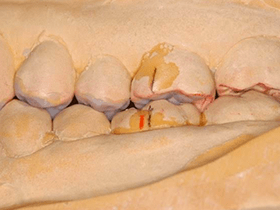

ある矯正治療後の患者様の治療例です。

矯正治療が終わって2年ほど経過してから、口を開けると顎がガクガクなるそうです。

耳の近くに少し痛みもあるようでした。

歯並びも美しく、矯正治療に問題があるようには見えません。

しかし、咬み合わせの分析を行うと、生理的な咬み合わせに歪みが生じていました。

歯がすり減ってしまい奥歯の裏側に隙間があります。 これでは咬んだ時に顎が横にずれてしまい、しっかりと咬めません。